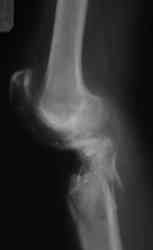

На консультацию обратилась женщина, 23 года. В феврале огнестрельное ранение колена.

Снимки первичные и майские в приложении. А также внешний вид раны. Укорочения конечности нет. Разгибание в коленном суставе отсутствует. Сгибание сохранено. Нестабильности нет.Дно раны - мертвая кость.

Ходит на костылях, приступая на ногу. Какие у кого есть соображения по лечению, в частности по способу восстановления собственной связки надколенника?